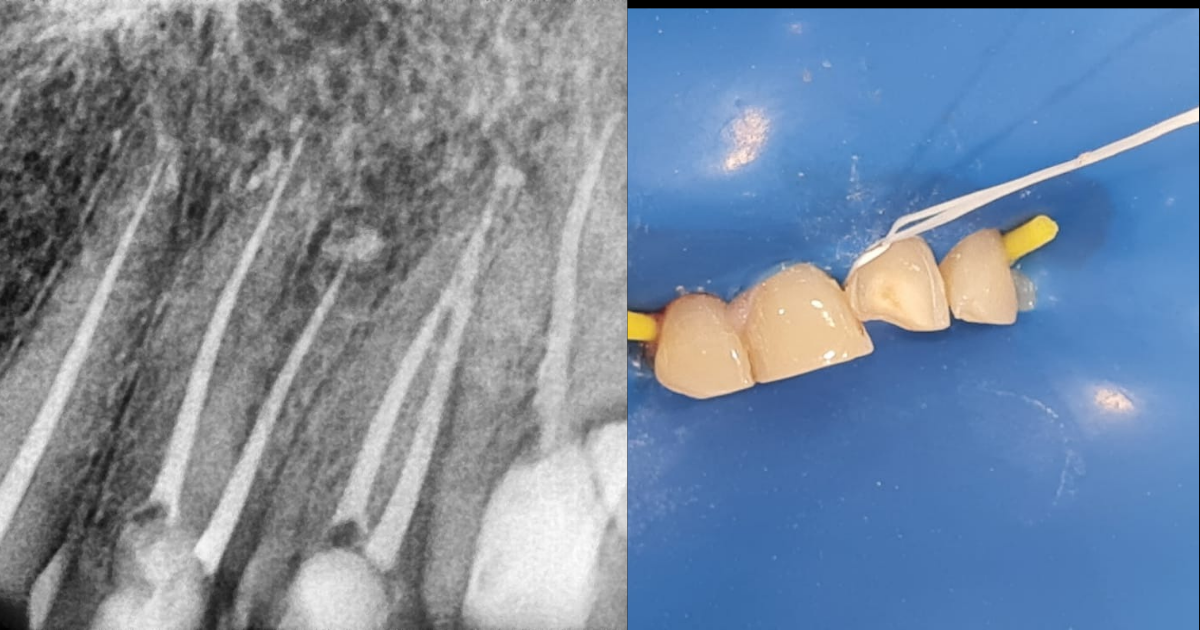

5. High Quality Restorative Work

Rebuilding the structure and function of the tooth after the root canal is very important to prevent reinfection. This is achieved by restoring with a strong filling or a crown to improve the prognosis of the tooth.

4. The Coronal Seal

How the tooth is sealed after cleaning and shaping is as important as any other step.

Even a perfect root canal can fail if the restoration leaks, allowing bacteria from the mouth to seep back into the roots. This is why most dentists insist on a permanent crown shortly after treatment to provide a tight seal and structural support.